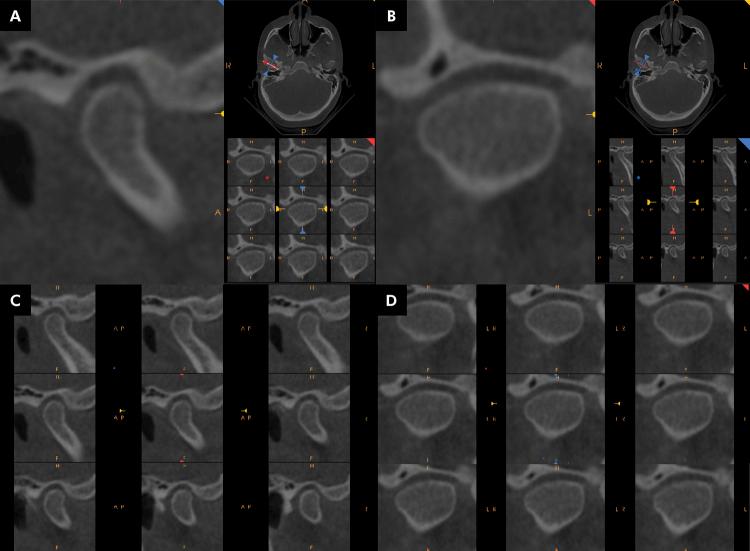

This observational, cross-sectional study with retrospective collection was aimed to evaluate the prevalence of morphological changes in mandibular condyles in individuals with class II malocclusion, classified according to different vertical growth patterns (brachyfacial, mesofacial, and dolichofacial), through cone beam computed tomography (CBCT). Seventy CBCT images (140 mandibular condyles) were selected from individuals without orthodontic treatment, of both sexes, aged between 25 and 50 years. No statistically significant differences were found between facial patterns; however, there was a higher relative prevalence of bone changes in dolichofacial individuals with flattening (62%), sclerosis (44%), and subchondral bone cyst (20%). Erosion and osteophytes prevailed in mesofacial (39%), and brachyfacial individuals (32%), respectively. Thus, there was no statistically significant difference in the prevalence of degenerative changes between the vertical skeletal patterns. Flattening was the most prevalent change, whereas subchondral bone cyst was the least prevalent among the three groups studied. The observational design of this study makes it possible to analyze image banks to verify the correlation of morphological changes in the temporomandibular joint in different facial patterns in patients with class II malocclusion. A limitation of the study is that clinical characteristics were not evaluated.

这项采用回顾性收集数据的观察性横断面研究旨在通过锥形束计算机断层扫描(CBCT)评估安氏II类错牙合个体中,根据不同垂直生长模式(短面型、平均面型和长面型)分类的下颌髁突形态变化的患病率。从年龄在25至50岁之间、未经正畸治疗的男女个体中选取了70张CBCT图像(140个下颌髁突)。面部模式之间未发现统计学上的显著差异;然而,长面型个体中出现骨质改变(变平占62%、硬化占44%、软骨下骨囊肿占20%)的相对患病率较高。侵蚀和骨赘分别在平均面型个体(占39%)和短面型个体(占32%)中更为常见。因此,垂直骨骼模式之间退行性改变的患病率没有统计学上的显著差异。变平是最常见的改变,而软骨下骨囊肿是所研究的三组中最不常见的。本研究的观察性设计使得分析图像库以验证安氏II类错牙合患者不同面部模式下颞下颌关节形态变化的相关性成为可能。该研究的一个局限性是未评估临床特征。